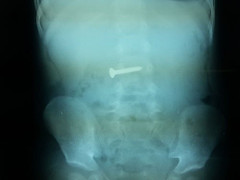

Một bé trai 2 tuổi ở Nghệ An vừa được các bác sỹ cấp cứu kịp thời và gắp thành công dị vật là chiếc ốc vít ra khỏi cơ thể.